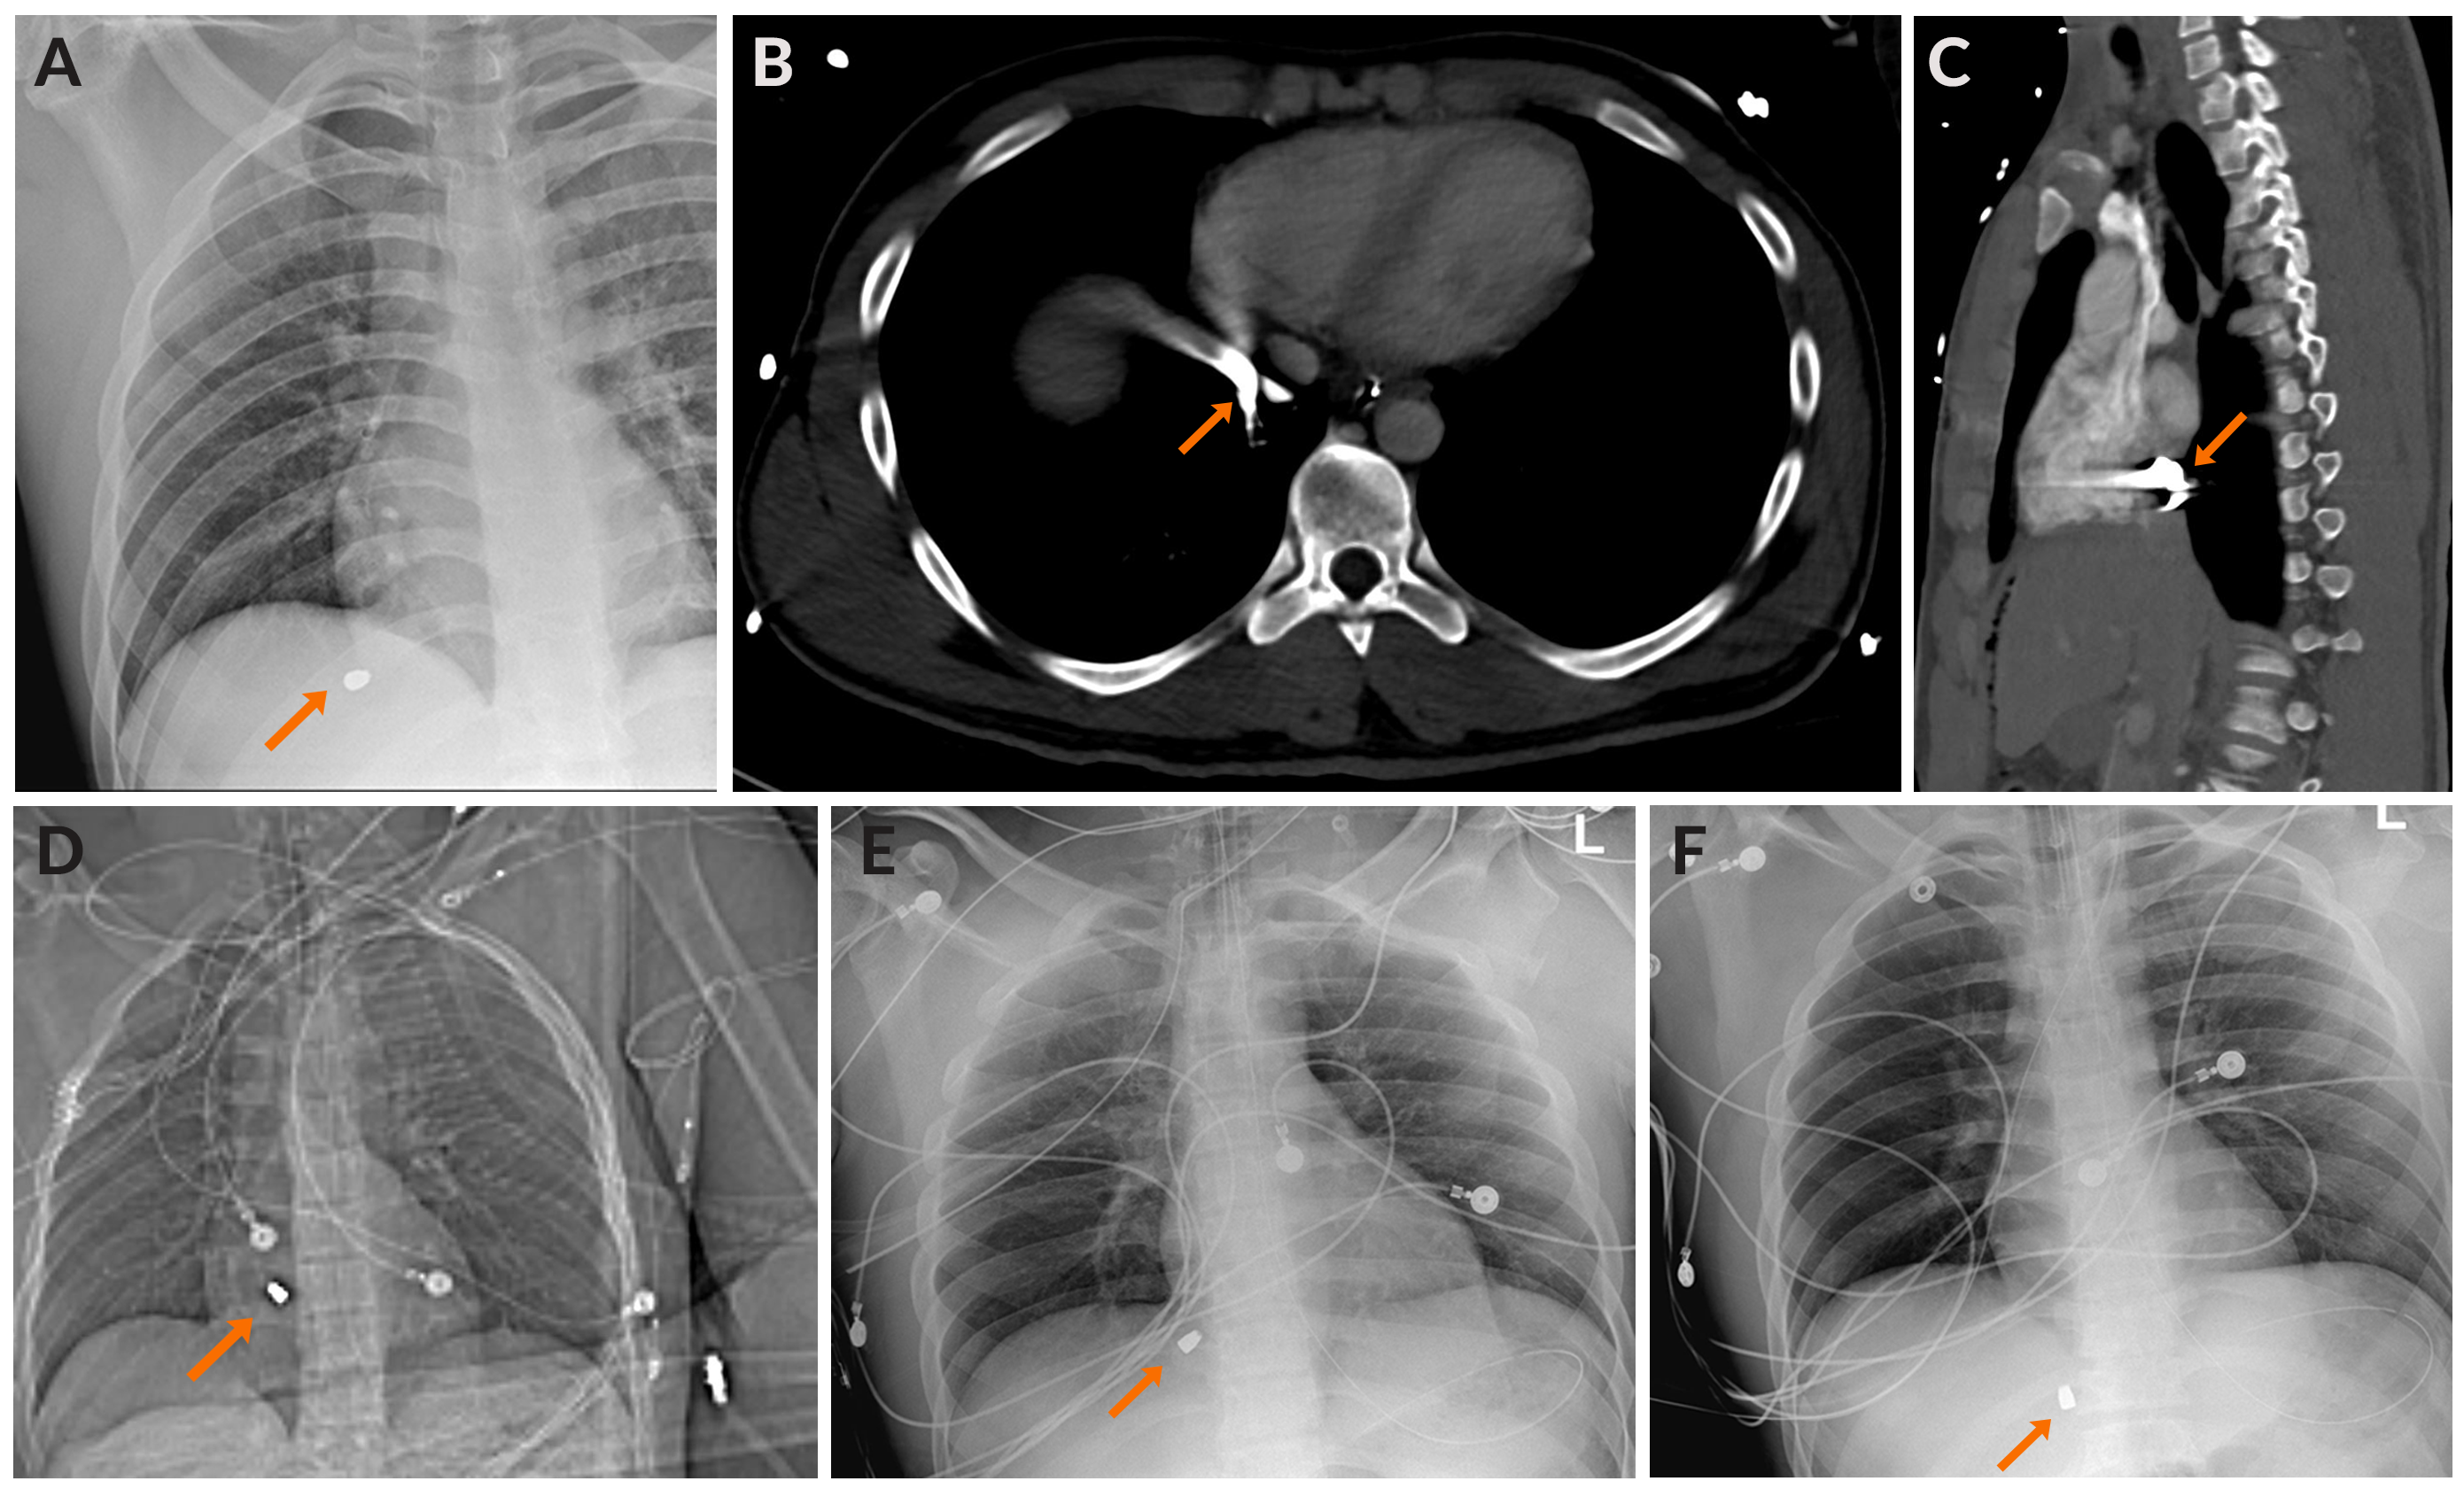

An extended focused assessment with sonography for trauma was positive for intra-abdominal fluid, likely blood products. Radiographs of the chest, abdomen, and pelvis were performed, and a bullet was noted in the high right upper quadrant of the abdomen under the right hemidiaphragm (Figure 2A). No exit wound was seen on physical exam.

The patient was brought to the computed tomography (CT) scan room for a CT of the chest, abdomen, and pelvis following trauma and urogram protocols. The scan was notable for a metallic bullet at the inferior cavoatrial junction (ICAJ). Subsequent chest radiographs demonstrated slight variation of the bullet, suggesting mobility and an intravascular location. The bullet projected over the upper IVC in multiple locations, also indicating mobility (Figure 2B-F).